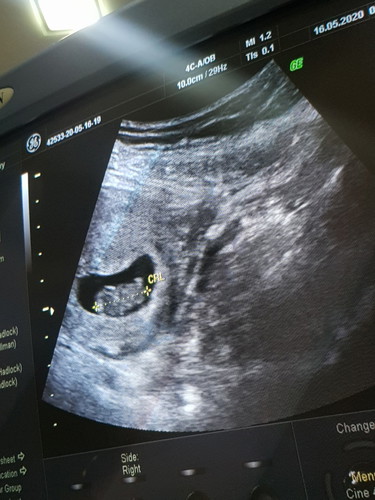

8w5d ไปซาวมาแขนขาดุกดิ๊กเลยค่ะ แต่ยังต้องฉีดยากันแท้งอยู่เพราะท้องที่แล้วแท้ง ท้องนี้ก็ยังกลัวๆอยู่เลยค่ะ แม่ๆบ้านไหนเคยแท้ง ท้องใหม่แล้วกังวนไหมค่ะ